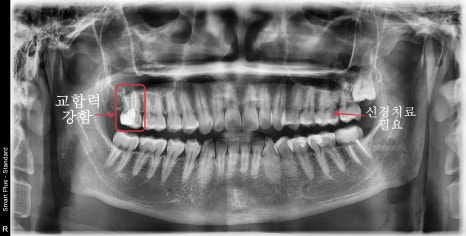

초진 엑스레이, 구강 내 사진입니다

과거에 신경치료 완료 후 보철치료 없이 레진으로만 마무리된 케이스입니다.

시간이 지나 치아의 파절이 생기며 주변으로 2차 우식이 진행되고

안쪽으로는 미세한 크랙라인도 관찰되었습니다.

통증은 없으시지만 추가적인 파절을 막기 위해 기존 재료를 제거하고 다시 수복하여 보철치료를 진행하며

반대편 안쪽으로 진행된 충치에 의해 신경치료가 필요했습니다.

겉에서는 안쪽이 살짝 어둡게 보였지만

엑스레이상에서는 이미 신경까지 충치가 진행돼있었습니다